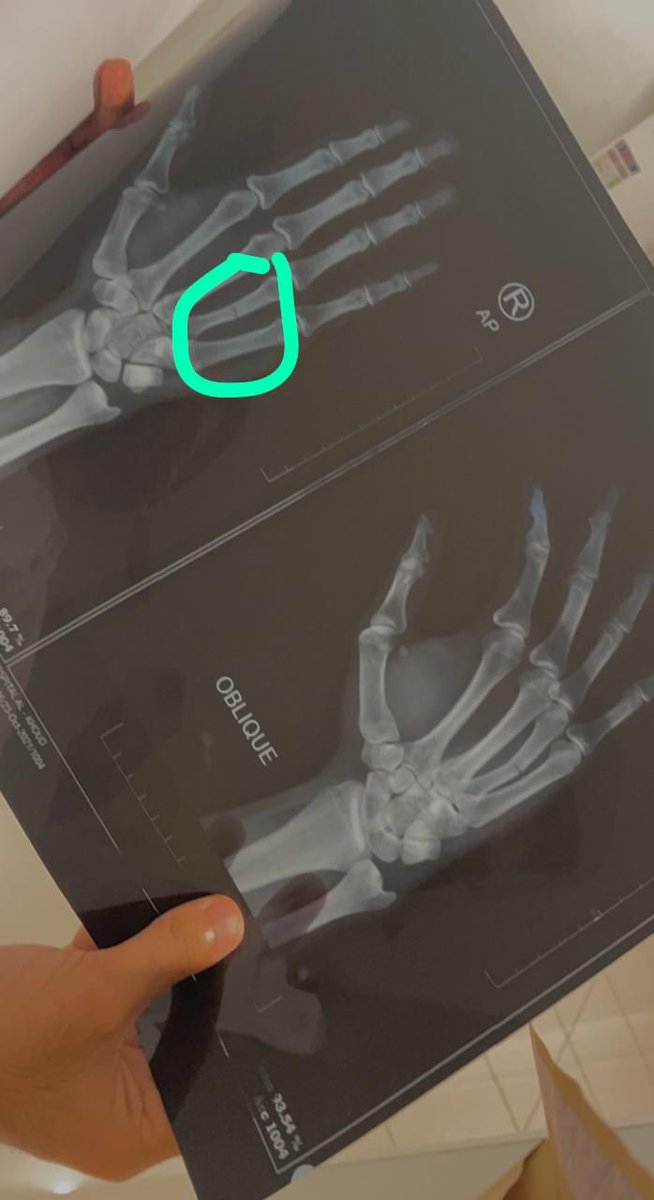

واللي زاد الطين بله انه بعد اسبوعين من بداية الروتيشن انكسرت ايدي وتبهدلت حرفياً شهرين بذاك الجبس وايدي اليمين، لا عارف اكتب شي، ولا عارف افحص المرضى، والبعض م يعذروك استغربهم!!

اما بعض الدكاترة صراحة ع عيني وراسي كانوا يعطوني عذري ❤️❤️.